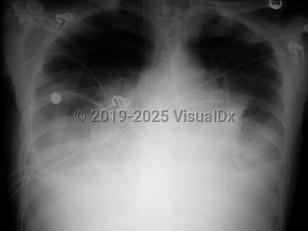

Chest pain, Dyspnea, 50-59 year old Female